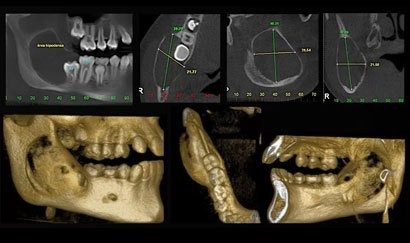

TOMOGRAFIA COMPUTADORIZADA CONE BEAM